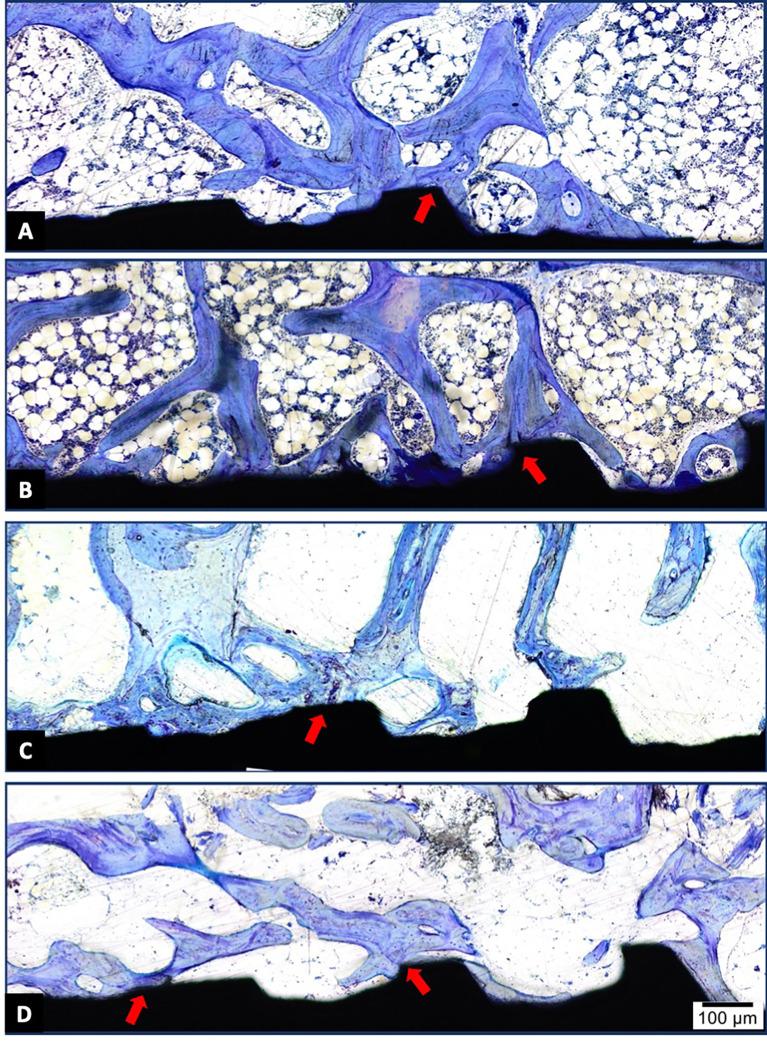

Hydroxyapatite used as a coating for titanium dental implants reduces the time required for osseointegration. Platelet-rich fibrin (L-PRF) releases growth factors and cytokines, enhancing tissue healing and bone regeneration. This study aimed to evaluate histologically, histomorphometrically, and by microcomputed tomography an implant surface coated with nanostructured hydroxyapatite (HAnano), in comparison with a double acid-etched (DAA) surface, both with and without peri-implant grafting with L-PRF, installed in over-instrumented sites in a low-density bone. Five adult sheep (2-4 years old) received twenty 3.5 × 10 mm implants in the iliac crest. Bone-to-implant contact (BIC) and bone-occupied area fraction (BAFo) were evaluated histomorphometrically after an 8-week experimental period. Brown-Forsyth analysis of variance (ANOVA) and Welch's ANOVA test did not identify significant differences between the experimental groups. On average, BIC ranged from 44% (HAnano + L-PRF) to 63% (DAA + L-PRF). µCT analysis revealed that bone volume density in the peri-implant region ranged from 26% (HAnano + L-PRF) to 39% (DAA). No statistically significant differences were observed between the groups. Both implant surfaces studied allowed osseointegration in low bone density sites, independently of peri-implant grafting with L-PRF, after 8 weeks of implantation. While this model provided controlled conditions for evaluating early-stage osseointegration, the absence of functional loading and the relatively short follow-up period should be considered when extrapolating the findings to clinical applications. Future studies should assess these variables under load-bearing conditions with extended observation periods. All the sheep in this study remained alive.

用作牙科钛植入物涂层的羟基磷灰石可减少骨结合所需的时间。富血小板纤维蛋白(L-PRF)可释放生长因子和细胞因子,促进组织愈合和骨再生。本研究旨在通过组织学、组织形态计量学以及微计算机断层扫描,评估一种涂覆有纳米结构羟基磷灰石(HAnano)的植入物表面,与双重酸蚀(DAA)表面相比,在低密度骨的过度预备部位植入时,有无L-PRF进行种植体周围植骨的情况。五只成年绵羊(2 - 4岁)在髂嵴植入20枚3.5×10毫米的植入物。在8周的实验期后,通过组织形态计量学评估骨与植入物接触(BIC)和骨占据面积分数(BAFo)。Brown-Forsyth方差分析(ANOVA)和Welch's ANOVA检验未发现实验组之间存在显著差异。平均而言,BIC范围为44%(HAnano + L-PRF)至63%(DAA + L-PRF)。µCT分析显示,种植体周围区域的骨体积密度范围为26%(HAnano + L-PRF)至39%(DAA)。各实验组之间未观察到统计学上的显著差异。植入8周后,所研究的两种植入物表面均可在低骨密度部位实现骨结合,与是否使用L-PRF进行种植体周围植骨无关。虽然该模型为评估早期骨结合提供了可控条件,但在将研究结果外推至临床应用时,应考虑缺乏功能负荷以及随访期相对较短的问题。未来的研究应在负重条件下并延长观察期来评估这些变量。本研究中的所有绵羊均存活。